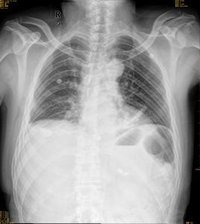

肺梗塞肺栓塞可由普通X線平片、血管造影、CT和MR以及核素掃描等方法檢查。

肺動脈小分支的單發肺栓塞X線可無異常表現,大分支及多發性小分支栓塞X線可見X線異常表現。

(1)肺缺血:當肺葉或肺段動脈栓塞時,相應範圍的肺紋理減少或消失,透亮度增加,稱為韋斯特馬克(westmark)征。多發性小動脈栓塞引起廣泛性肺缺血。

(2)肺動脈異常:病變的肺動脈因血栓嵌塞而增粗,其遠端因血流減少而變細。SCT顯示明確.

(3)肺體積減小:下葉肺栓塞多見,故肺體積縮小也於下葉常見,引起膈升高,肺門及葉間裂下移。並可合併盤狀肺不張。

(4)心影增大:心影增大由右室增大所致,見於較大肺動脈的栓塞或多發肺栓塞。

X線,SCT和MRI可以得以明確。

血管造影、核素掃描等也可以幫助診斷。